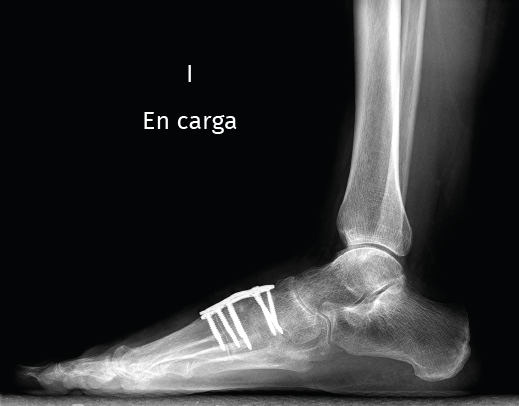

Figura 3. Imagen radiológica sagital donde se objetiva la consolidación en buena posición de la artrodesis.

Existen distintas opciones de osteosíntesis con tornillos y/o placas. Actualmente, disponemos de diferentes diseños de placas: placas de tipo “Pi” que fijan CMM1-CMM2, placas plantares, mediales, medioplantares o dorsales. Recomendamos el empleo de placas “Pi” si es preciso artrodesar CM-M2 y el uso de placas medioplantares o plantares para la artrodesis aislada de CM-M1, que desde el punto de vista biomecánico son más apropiadas (Figuras 1 a 3). Otro tema de debate es el empleo de injerto óseo esponjoso autólogo o de sustitutivos óseos como la matriz ósea desmineralizada o trifosfatos cálcicos. Recomendamos, especialmente en pacientes menores de 50 años, el empleo de injerto autólogo de cresta ilíaca.